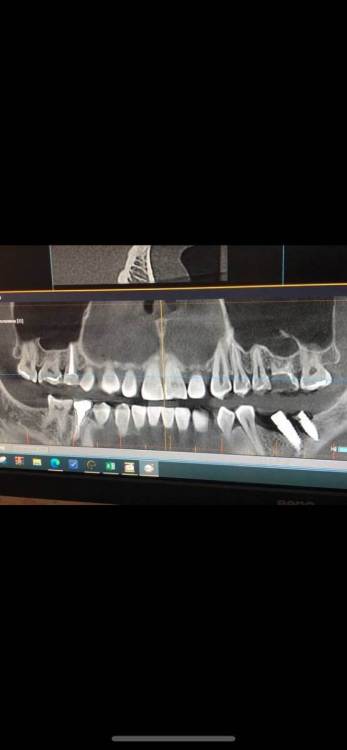

Stoyana Опубликовано 22 мая, 2023 Поделиться Опубликовано 22 мая, 2023 Здравствуйте ! Прошу прокомментировать замену имплантов . 10 лет назад были установлены 2 импланта , 6 на место удаленного зуба , и 7 - в качестве антагониста верхней 7 . Устанавил тот же доктор , по гарантии . Приняли решение заменить импланты , так как коронка с 6 сломалась , на 7 сломался абатмент . После операции , очень болит 5 , ноющая боль , плюс болезненные ощущения при глотании , болит челюсть в области операции . Доктор утверждает что по снимку проблем нет . Прошу прокомментировать ситуацию . Первые 2 фото - импланты которые заменили . 3 и 4 фото - новые импланты Ссылка на комментарий